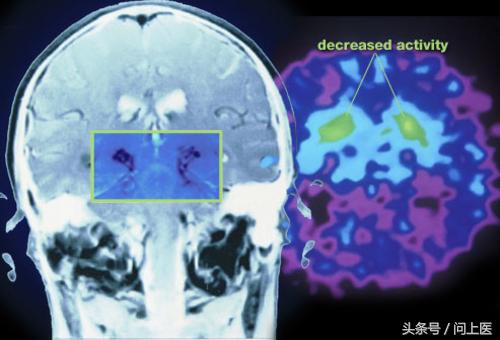

9 / 24 帕金森的诊断

医生一般不会使用大脑扫描来诊断帕金森,但是常常会用它来排除其他病症。为了确诊帕金森,医生可能会进行如下的检查:让检查者尝试运动手脚,检查运动缓慢;让手指静止观察震颤;在检查者放松状态下,医生会移动检查者的脖子、手臂和腿,检查是否僵硬;站立并轻轻地向后倒,检验平衡感。

在脑干中有个区域被称为黑质,黑质能控制行为。帕金森病患者中黑质中的细胞会停止生成多巴胺(一种神经传导物质,可帮助细胞传送脉冲),这些生成多巴胺的细胞死亡后,大脑就接收不到身体何时该动、怎样动的信息了。